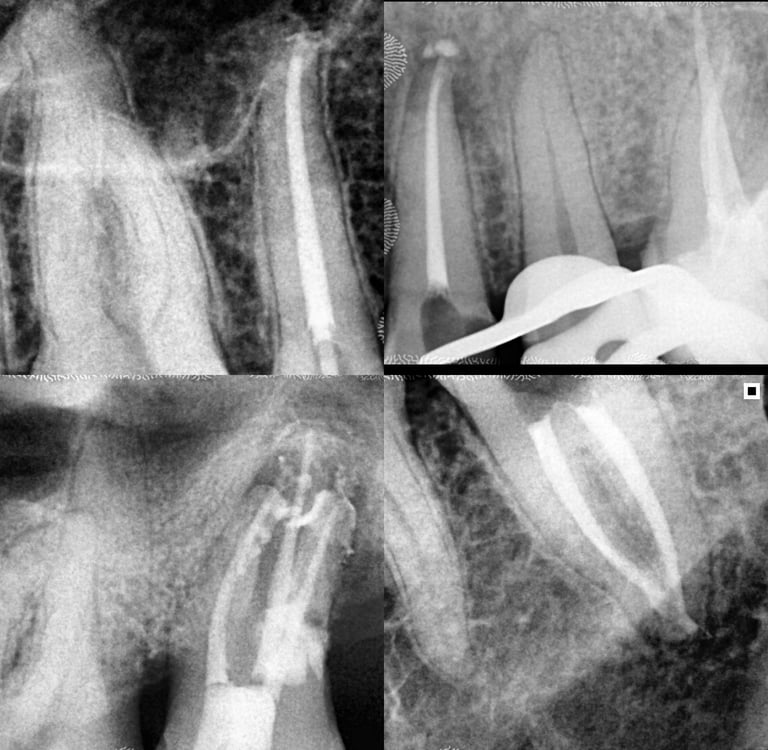

Em alguns casos, a necessidade de tratamento de canal é identificada em exames radiográficos, mesmo antes de o paciente sentir dor.

As radiografias periódicas podem revelar lesões na ponta da raiz, indicando um foco de infecção que precisa ser tratado.

Nesses casos, apenas o tratamento endodôntico é capaz de eliminar o problema e restaurar a saúde do dente.

Galeria

Na odontologia, cada sorriso é único e o resultado final depende de fatores biológicos individuais. Imagens clínicas não constituem promessa de resultado. Planejamento técnico e diagnóstico são fundamentais para o sucesso do tratamento."